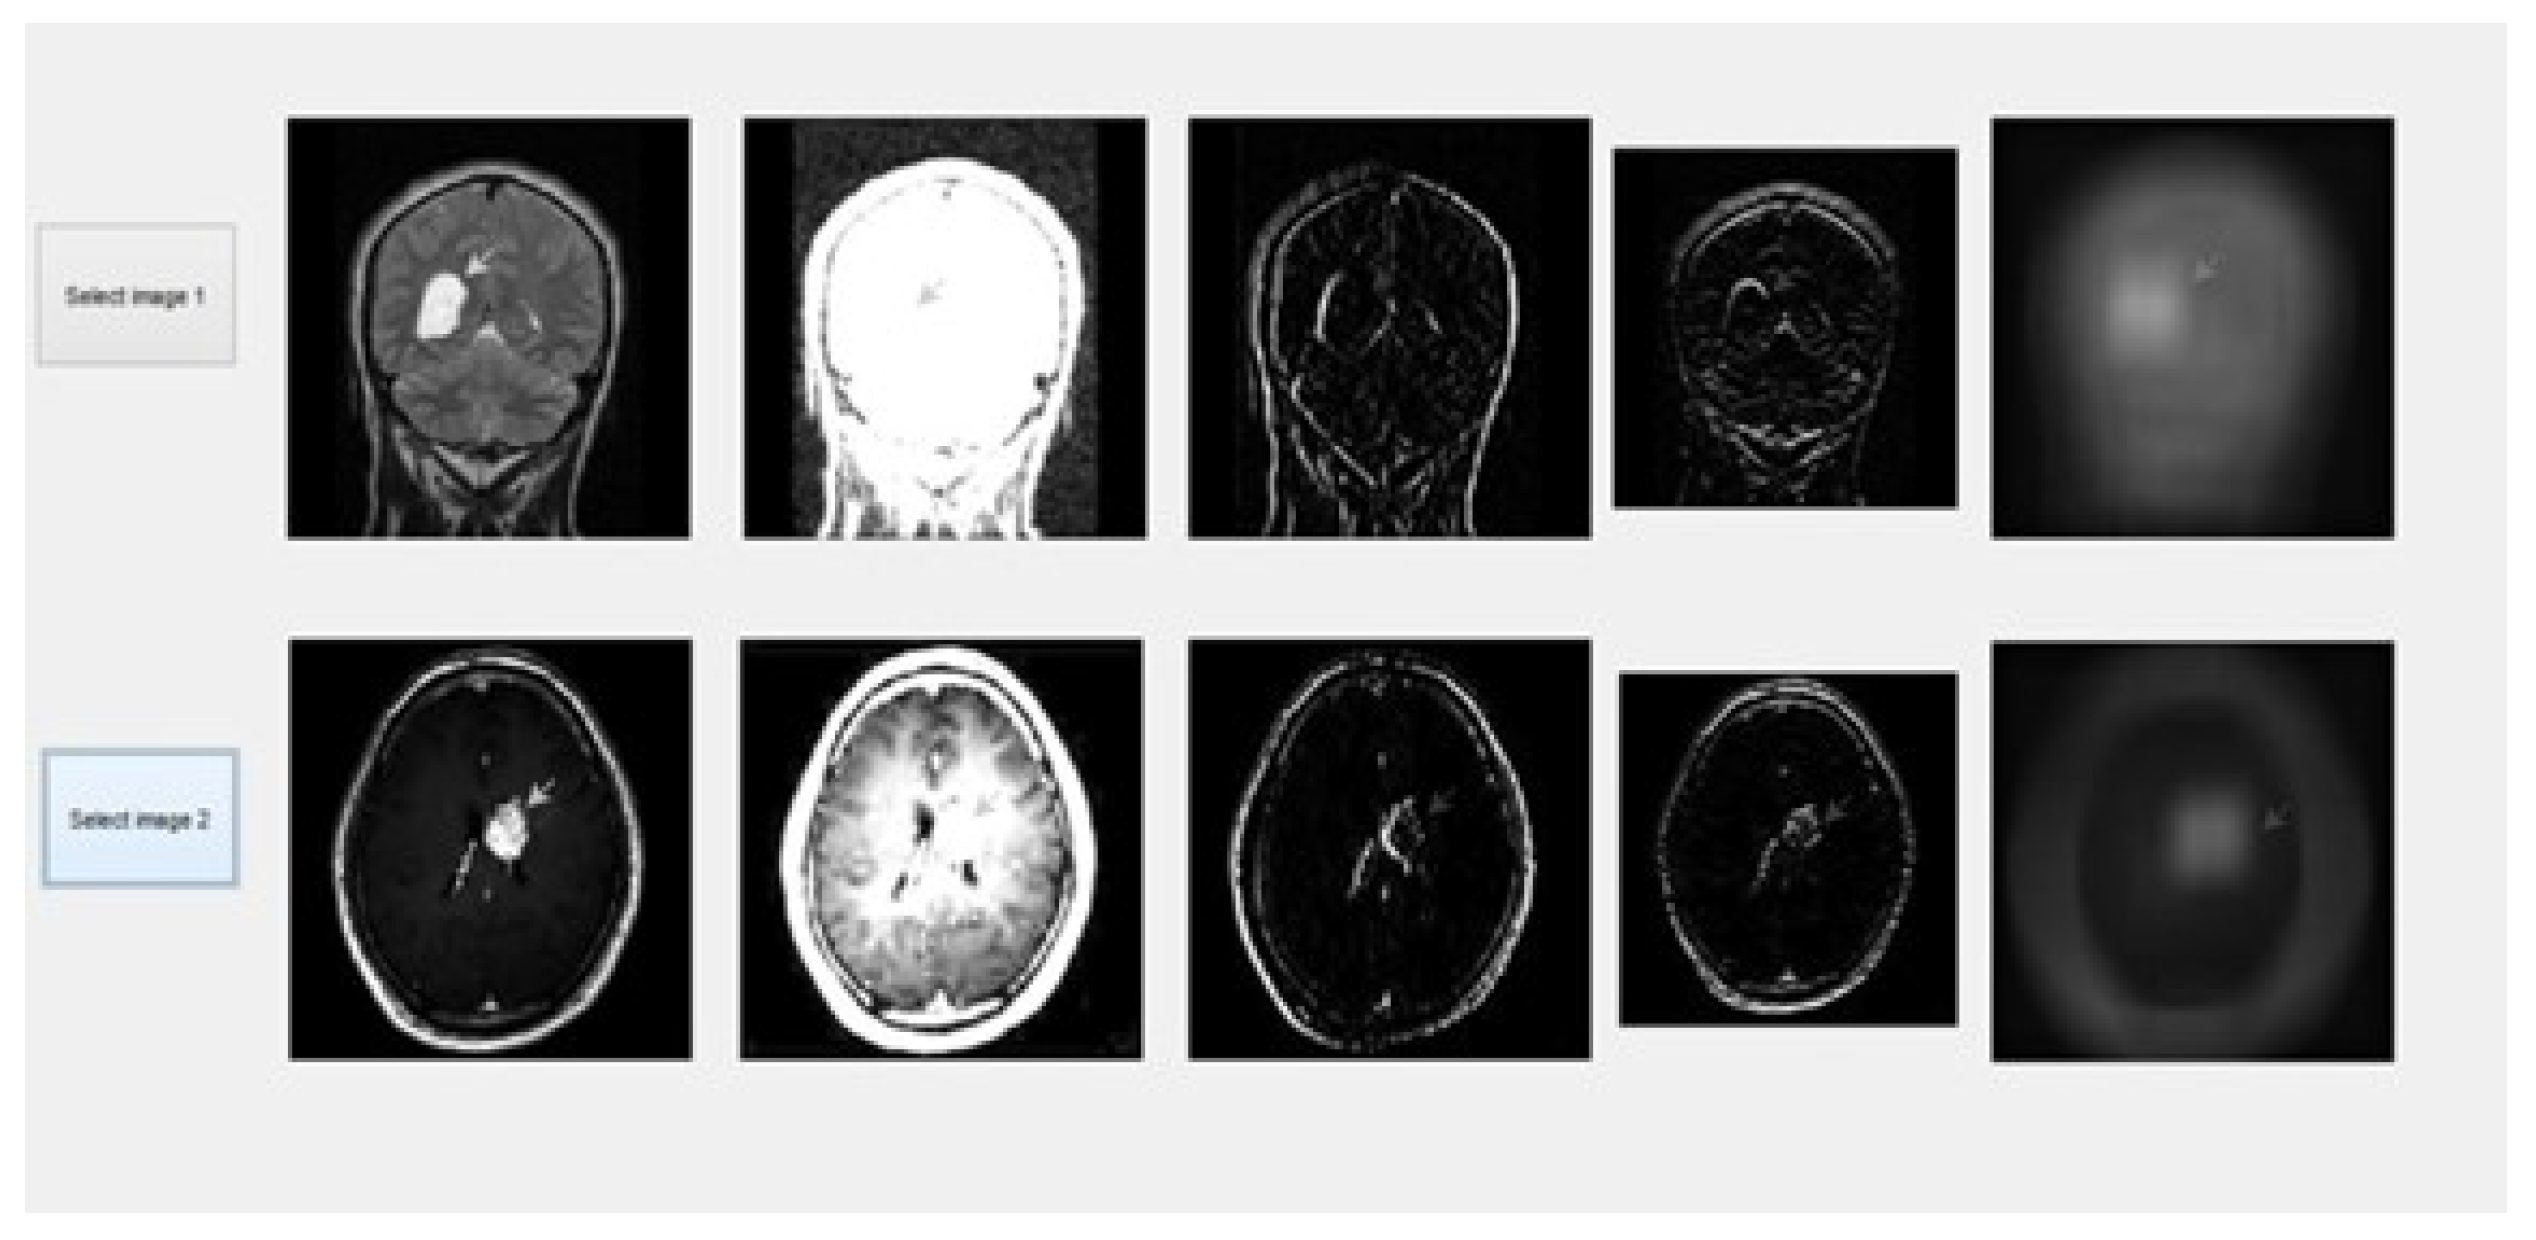

After introducing hybrid algorithms “(DCT, SWT, IHS, PCA, average)”, the next step was to implement them. To do this, we employ the “C programming” language. This code was included using MATLAB. The rule-based inclination combination in the “Dual-Tree Complex Wavelet” region was accomplished using various images from a standard image database and constant images as shown in Figures as shown in Figure 7, Figure 8 and Figure 9. The effectiveness of the suggested combination approach is demonstrated strongly with specific images, such as “multi-sensor images”, “multispectral remote detection” images, clinical images, “CT”, “MR images”, and “surreal images” [47]. We may also blend ongoing images.

Figure 7. Two medical scan images which are to be fused.

Information 15 00612 g007